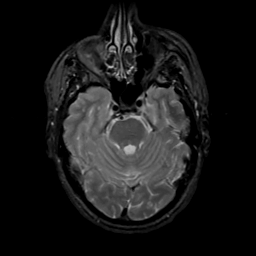

MR Study #16, June 23, 1991 -- Slice #15

[Home][Help][Clinical][Tour 1][Tour 2] Slice 15